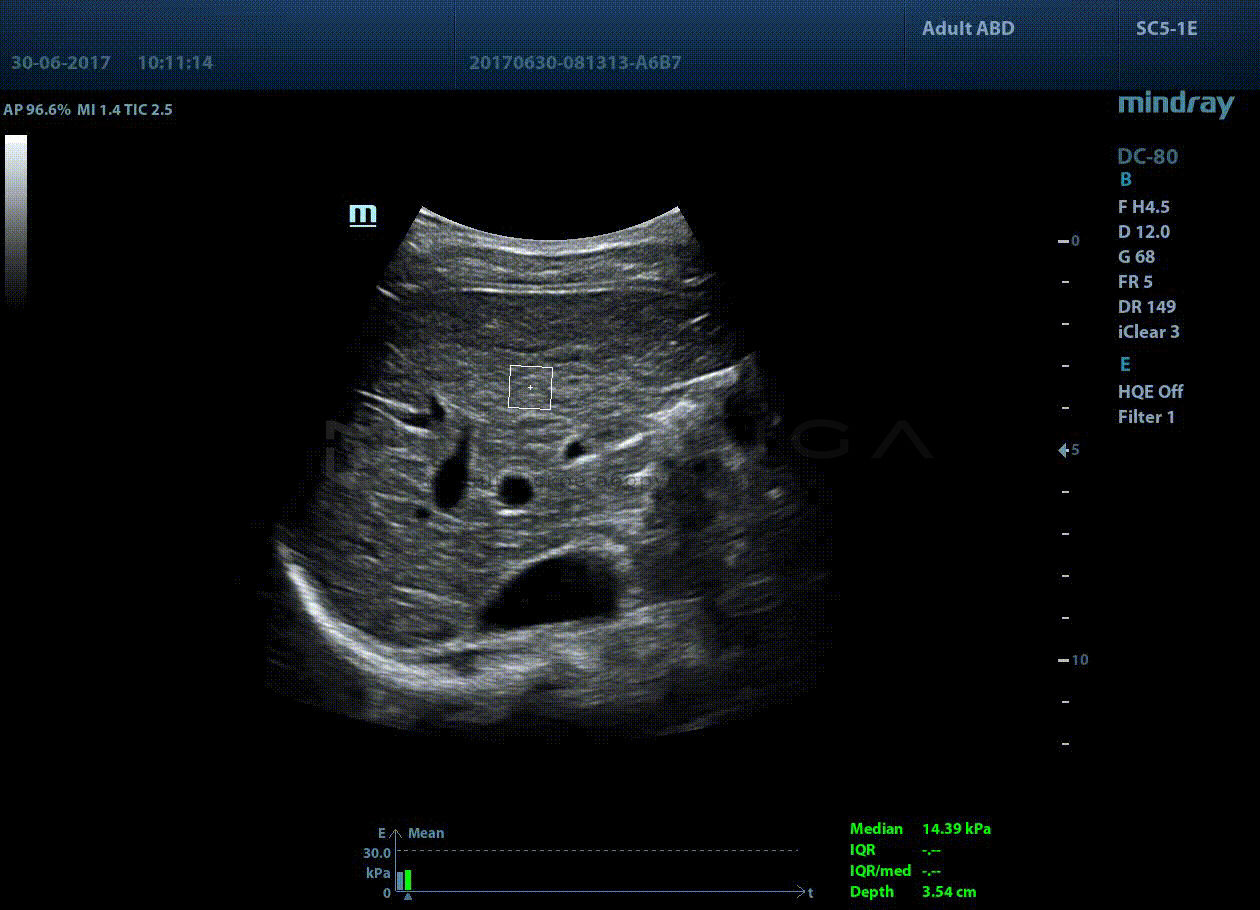

STQ (Sound Touch Quantification)

Sound Touch Quantification (STQ) позволяет быстро в режиме реального времени оценить жесткость ткани печени и определить стадию фиброза.

Опция доступна:

- на линейных датчиках

- на конвексных датчиках